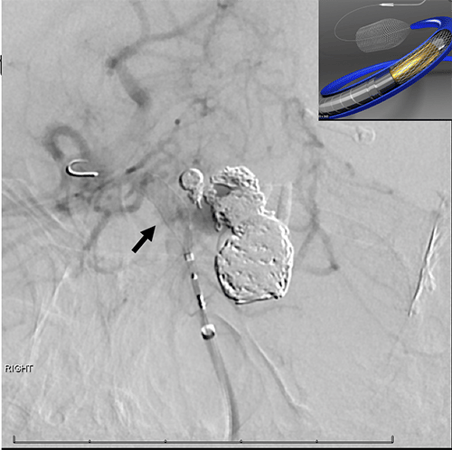

The pipeline flow diverter is another endovascular technique where instead of placing coils inside the aneurysm, a piece of cylindrical mesh is placed in the major blood vessel across from the aneurysm. It doesn’t get rid of the aneurysms immediately. Instead these pieces of mesh, known as stents, divert blood flow away from the aneurysms, increasing the possibility of clotting. In a few weeks or months, the aneurysm clots and is excluded from the circulation.

A pipeline flow diverter in the top of the basilar artery has only been described in literature maybe a handful of times before in children, and perhaps only about 20 times in adults. A flow diverter in this location has significant risks.

“It’s a very unusual method,” said Dr. Sacho.

The reason it’s not done very often is because the tiny blood vessels coming off the top of the basilar artery are very important — they keep the clockwork of your body alive. These may become inadvertently obstructed as a result of the flow diverter.

Dr. Sacho placed the pipeline flow diverter in the fall of 2020 during a three-hour procedure. Now 8 years old, Rosemary is four months post-surgery and doing great. The follow-up MRI scan showed the aneurysms have dramatically shrunk. The two small ones that were very difficult to treat are now gone, and the bigger one has shrunk by nearly a third and should close down completely in due time.